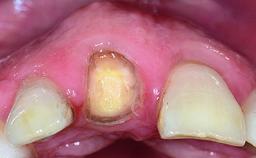

A 28-year-old patient presented at her general dentist’s office and complained about the appearance of her tooth 21. The patient had a history of trauma to this tooth. Endodontic treatment had been performed in the past and a crown placed on the tooth. A procedure to replace the old crown was performed by her dentist; however, a perforation on the middle third of the root occurred, and extraction of tooth 21 was suggested. Upon clinical and radiographic examination of the patient, who had been referred to us, replacement of tooth 21 by a dental implant appeared to be indicated.